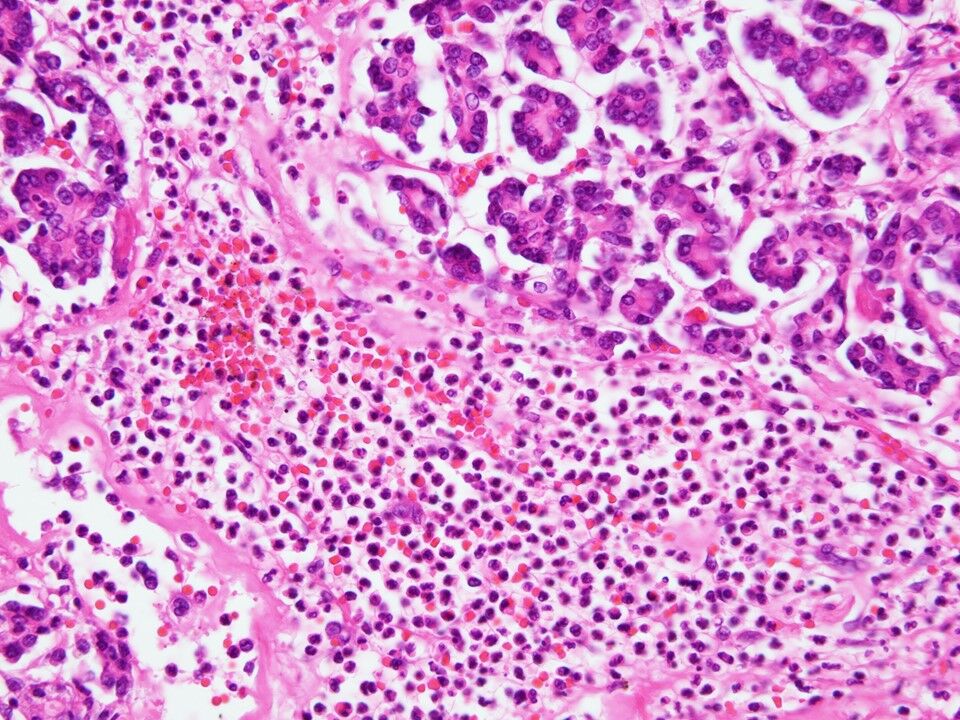

¼ðıÉô°Ì¤ÏÁ´¿È¤É¤³¤Ç¤â¤è¤¤¤¬¡¢ðôÉô¤¬Â¿¤¤¡£Â礤µ2 cm ̤Ëþ¡¤¼þ°Ï¤È¤ÎÌþÃå¤Ï¤ß¤é¤ì¤Ê¤¤¡¥¥ê¥ó¥ÑÀá¤ÎÁÈ¿¥Áü¤Ï¡Ö¿Í͡סÖ¿ºÌ¡×¡£¥ê¥ó¥ÑÀáÉÂÊÑÉô°Ì¤ÏÚÕÈé¼Á¡¤Èé¼Á¤ÎÁã¾õ¡ÁÍ»¹çÀÉÂÊÑ¡¥¹½À®ºÙ˦¤ÏÁÈ¿¥µå¡£¤³¤ì¤¬³ËÊø²õ»ºÊª¤òìÅ¿©¤¹¤ëÁÈ¿¥µå¤Î½Ð¸½¤¹¤ë¡£¤½¤Î¾¤Î±ê¾ÉºÙ˦¤âȼ¤¦¤³¤È¤¬¤¢¤ê¡¢ÁÈ¿¥µå¼çÂΤǤ¢¤ë¤¬¡¢´ðËܤÏ¿ºÌ¡á±ê¾ÉÁü¡£¤È¤¤Ë¾®¤µ¤Ê²õ»à¤òȼ¤¦¤³¤È¤¢¤ë¤¬¡¢´ðËÜÂ礤ʲõ»à¤Ï¤Ê¤¤¡£¿ÇÃÇ̾¤ÎÁÈ¿¥µåÀ¡Ö²õ»àÀ¡×¥ê¥ó¥ÑÀá±ê¤Î¡Ö²õ»à¡×¤Ï³ËÊø²õ»ºÊª¤òìÅ¿©¤¹¤ëÁÈ¿¥µå¤Î½Ð¸½¤ò¤µ¤¹¡£

¼Ì¿¿¤Ï·ë³ËÀ¥ê¥ó¥ÑÀá±ê¡£